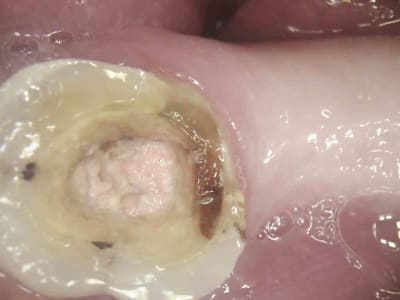

J'ai un de mes patients du cabinet où je travaillais avant qui m'a contacté car il a une reprise d'infection sous la CCM sur 46. Le praticien lui a déposé la couronne et va entreprendre le retraitement endodontique. Puis réaliser une nouvelle couronne. Etant donné que cela fait 3 ans que la couronne est posée le patient est mécontent. Il m'a appelé pour savoir s'il était possible d'avoir une indemnisation.

Je vous mets les photos en pièce jointe.

Ton endo était pas mal.

C'est étonnant que le matériau d'obturation qui était dense en 2011 se soit dégradé à ce point et si vite.

Il est possible qu'il y ait autre chose (perfo latérale un peu en dessous du plancher, fracture de la racine MV).

Par contre à ta place je ne contesterais rien du tout, t'es en tort à 300%. J'espère pour toi que toutes tes endos ne sont pas comme ça. Certains me diront que je suis sévère blablabla "ça t'es jamais arrivé de rater" etc, mais en sortant de la fac faire ça je trouve ça honteux.

Mets au moins un cône un minimum calibré. La gutta ne "disparaît" pas.

C'est quoi ce cone à 2 % ?

La radio post-op du 15/11/2011 semble montrer la présence de cône de gutta dépassant coronairement . L'erreur ne viendrait-elle pas d'une empreinte de l'ic dans la foulée .

la préparation a retiré les cônes laissant le ciment endodontique.